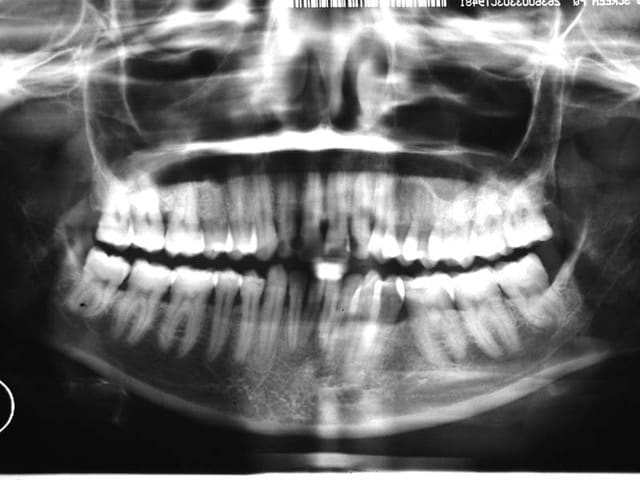

voici les Rx.

Au départ, il existait des Pbs. des deux cotés, inégalement répartis. maintenant le coté D. est bien, mais que dire du coté G. et du bloc Ant. qui évolue vers une Cl. II. 2, malgré une contention Inf.

comme quoi un TTT. ODF. peut présenter un joli résultat sur un secteur et désorganiser les autres secteurs

la contention Inf. ne peut pas empêcher l’évolution défavorable de ce cas

heureusement, je n’ai pas de Pbs. de d’ATM.

si j’arrive à redresser les arcades (reformage) et si je réouvre au niveau de 35, le Pb. se posera alors du remplacement de cette dent

cela fait beaucoup de si

voilà comment avec une extraction, on transforme un cas, au départ relativement simple, en cas compliqué